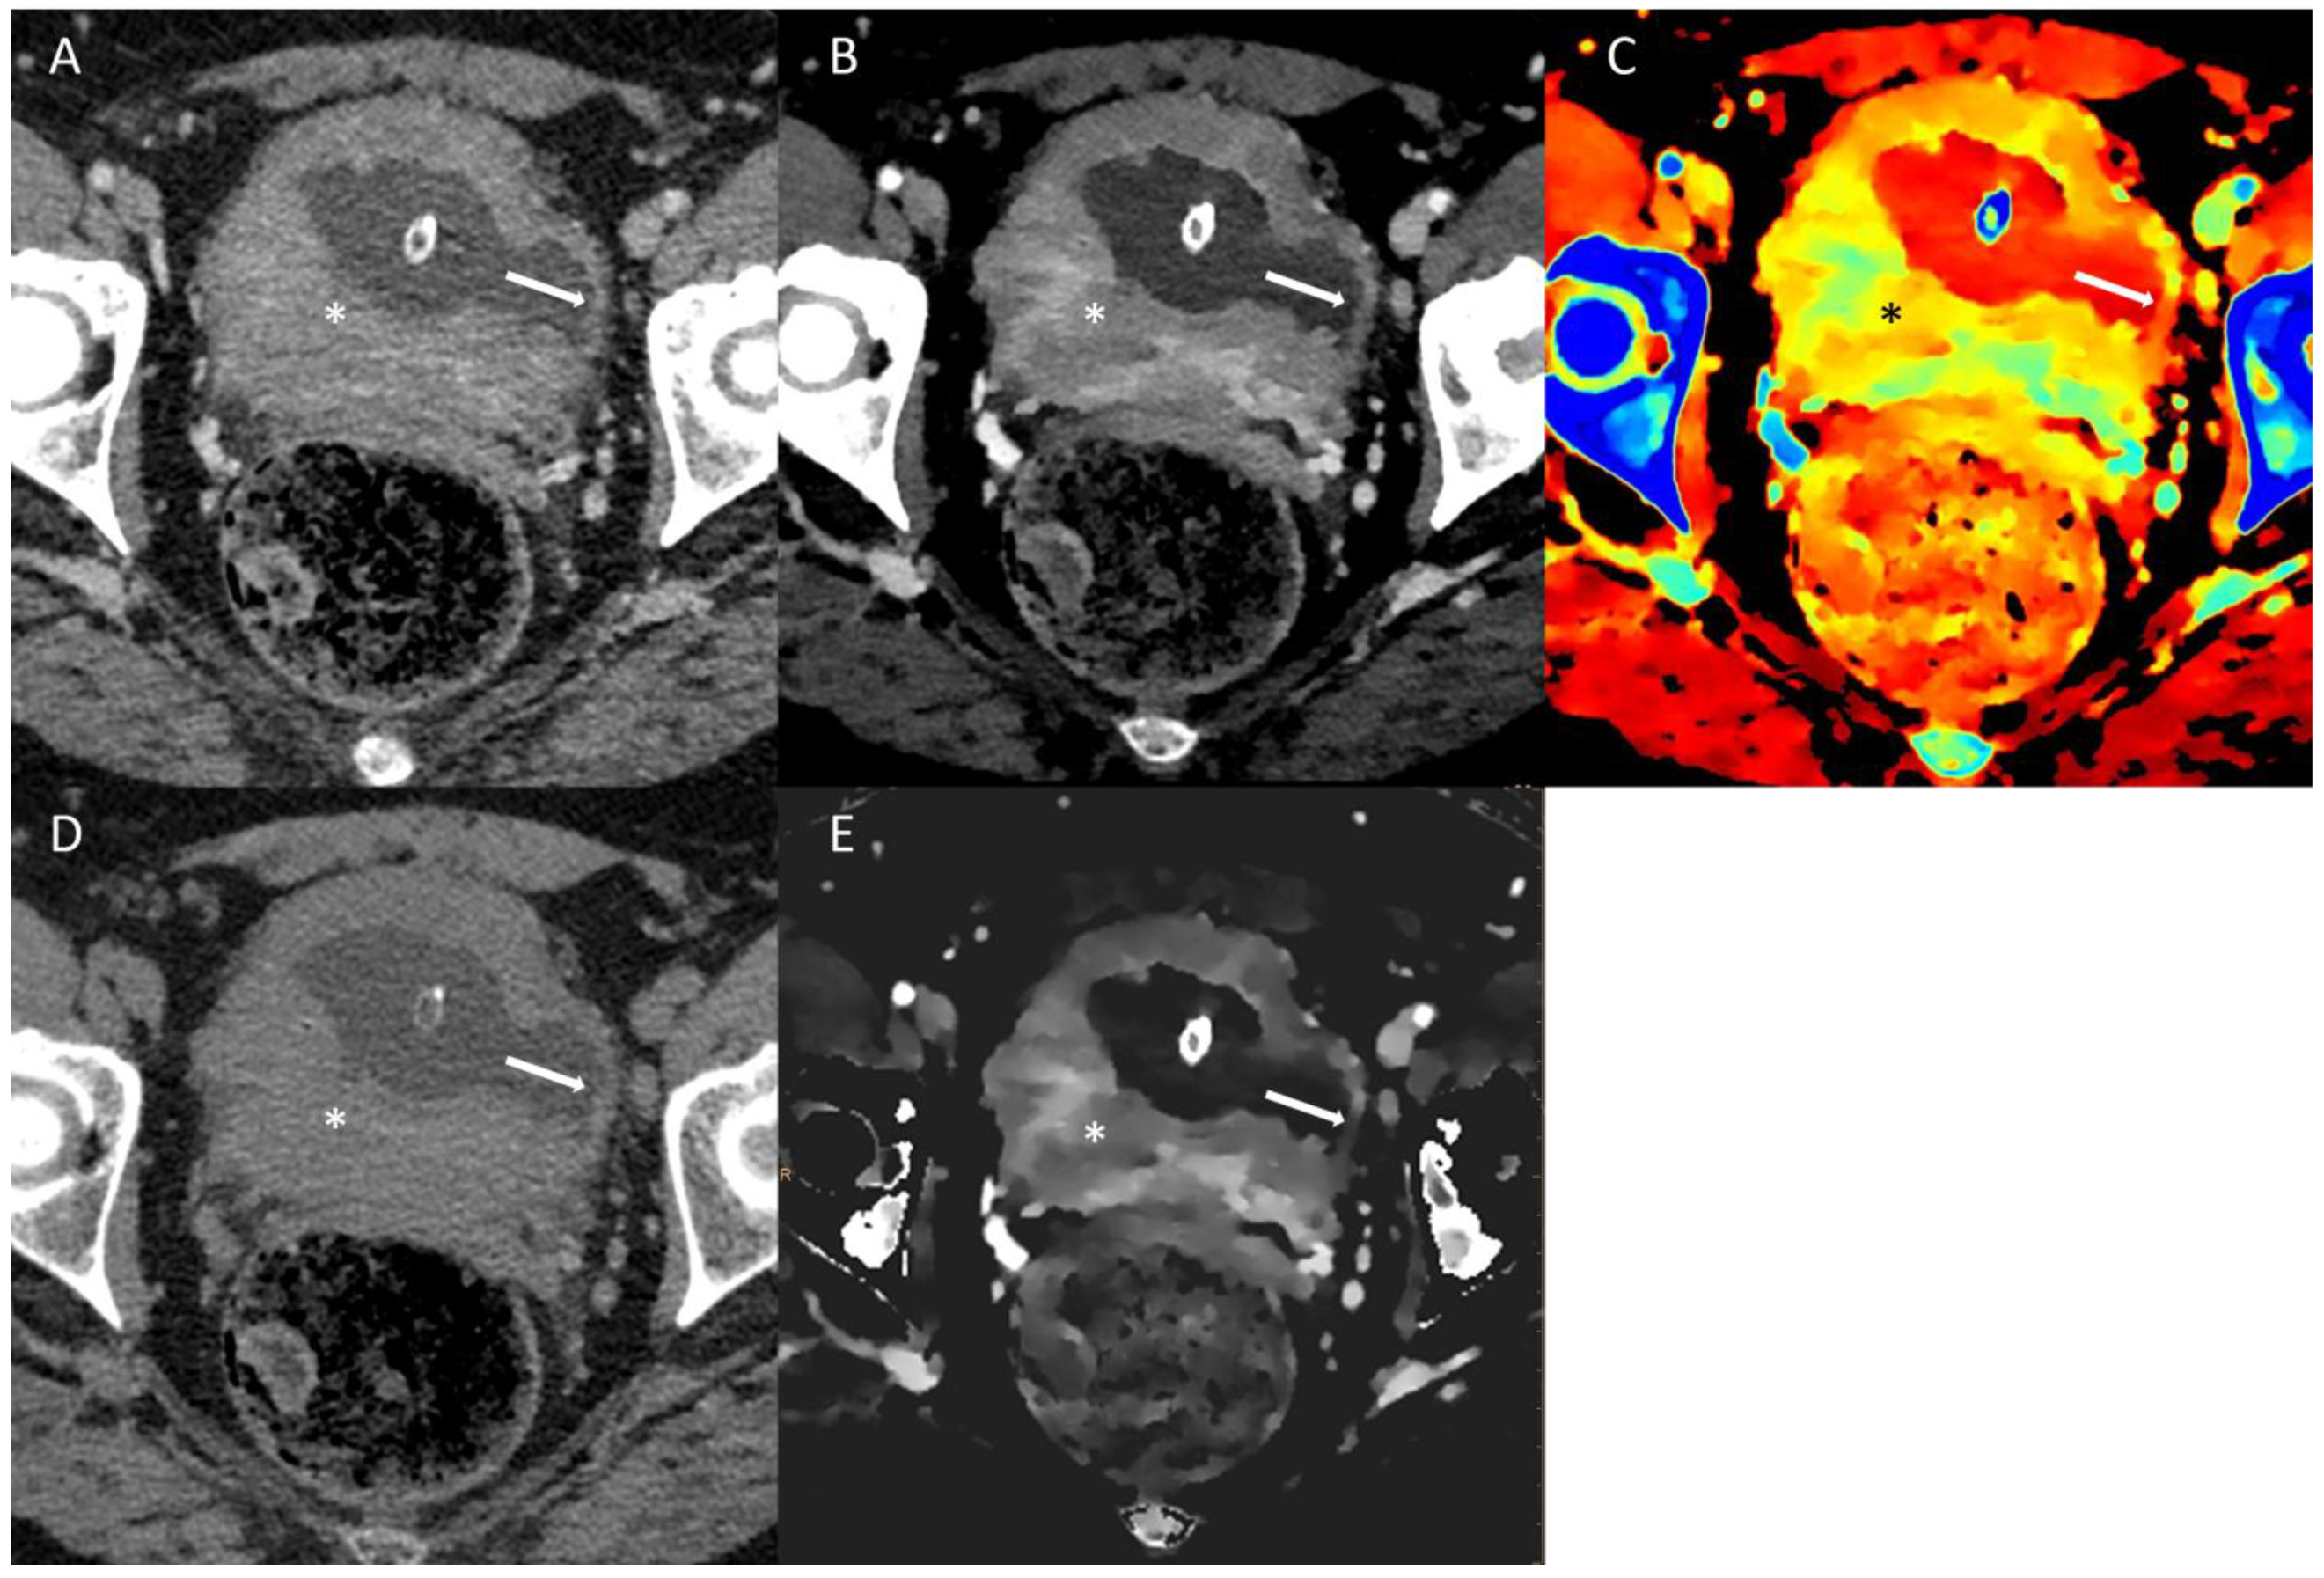

In the study by Bucolo GM and colleagues [25], the reliability of VNC images for evaluating renal masses was investigated in comparison to true non-contrast (TNC) images. The study involved the assessment of attenuation values and standard deviations by drawing regions of interest on both TNC and VNC images, which were reconstructed from corticomedullary (VNCc) and nephrographic (VNCn) phases. The results revealed differences in attenuation values of 74%, 18%, 5%, and 3% for TNC-VNCc and 74%, 15%, 9%, and 2% for TNC-VNCn. A Wilcoxon signed-rank test confirmed the equivalence of attenuation values between TNC and VNC images. Moreover, the diagnostic performance of VNC images in depicting kidney simple cysts remained high compared to TNC, with VNCc-AUC at 0.896 and VNCn-AUC at 0.901, while TNC-AUC stood at 0.903. Overall, the study demonstrated a strong agreement between the VNC and TNC images when assessing renal lesions. Specifically, in 92% of cases for VNCc and 89% for VNCn, the difference in attenuation values was less than 10 Hounsfield units (HUs) compared to TNC. While minor discrepancies were observed in a minority of cases, emphasizing the diagnostic value of TNC images, especially for the initial characterization of indeterminate renal masses, the VNC algorithm proved to be a reliable alternative in subsequent examinations. This approach offers significant benefits to patients in terms of radiation dose reduction [25]. An example of the spectral imaging of a challenging renal lesion can be found in Figure 2.

Figure 2. Conventional multi-energetic CT image in portal venous phase (A) of a small dense renal cyst (*) with a millimetric polypoid component (arrow). The cyst has a 49.2 HU density, thus barely visible in this image, so it is impossible to distinguish between a dense cyst and a hypovascular renal lesion. The 40 KeV Virtual Monoenergetic Image (B) shows poor changes in the enhancement of the cystic component and a good increase in the density of the polypoid component. Z-effective maps image (C) shows low atomic numbers within the cystic component and high numbers in the polypoid component. Virtual Non-Contrast image (D) shows no difference in the densitometry of the cystic component. Iodine density imaging (E) shows no iodine concentration in the cystic component and iodine concentration in the polypoid component. The lesion was classified as a class III Bosniak renal cyst, and afterwards, a multidisciplinary meeting was decided on for follow-up (mainly for dimensions). A control CT scan at 12 months (not shown) demonstrated no differences.